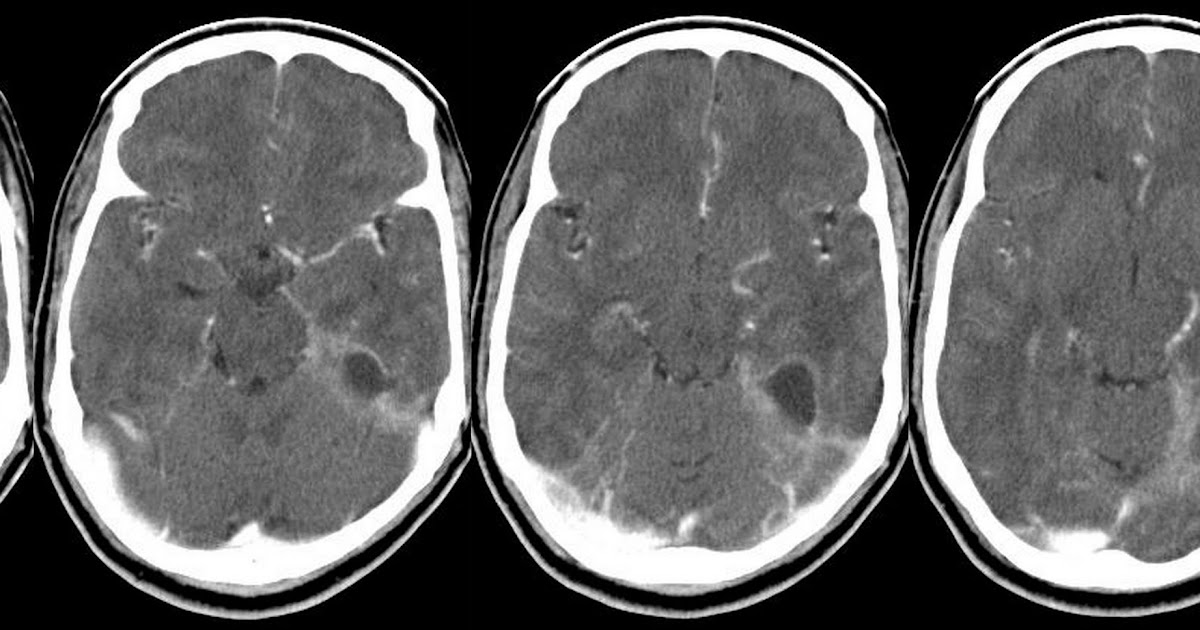

Субдуральный абсцесс

Субдуральный абсцесс 108 фотографий